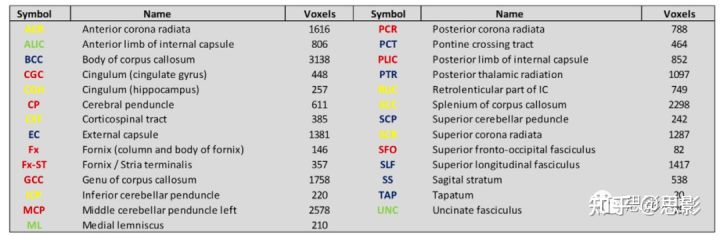

DTI指标

使用CAMINO扩散图像分析软件导出了HYDI数据的第一层(b值= 375 s/mm2)和第二层(b值= 1500 s/mm2)。DTI指标根据下面公式计算:

λ1, λ2和 λ3是扩散张量的本征值。FA描述了水扩散的相干性,即各向异性;MD描述了成像体素内的平均水扩散;AD描述平行于轴突方向的扩散;RD表示垂直于轴突的扩散。